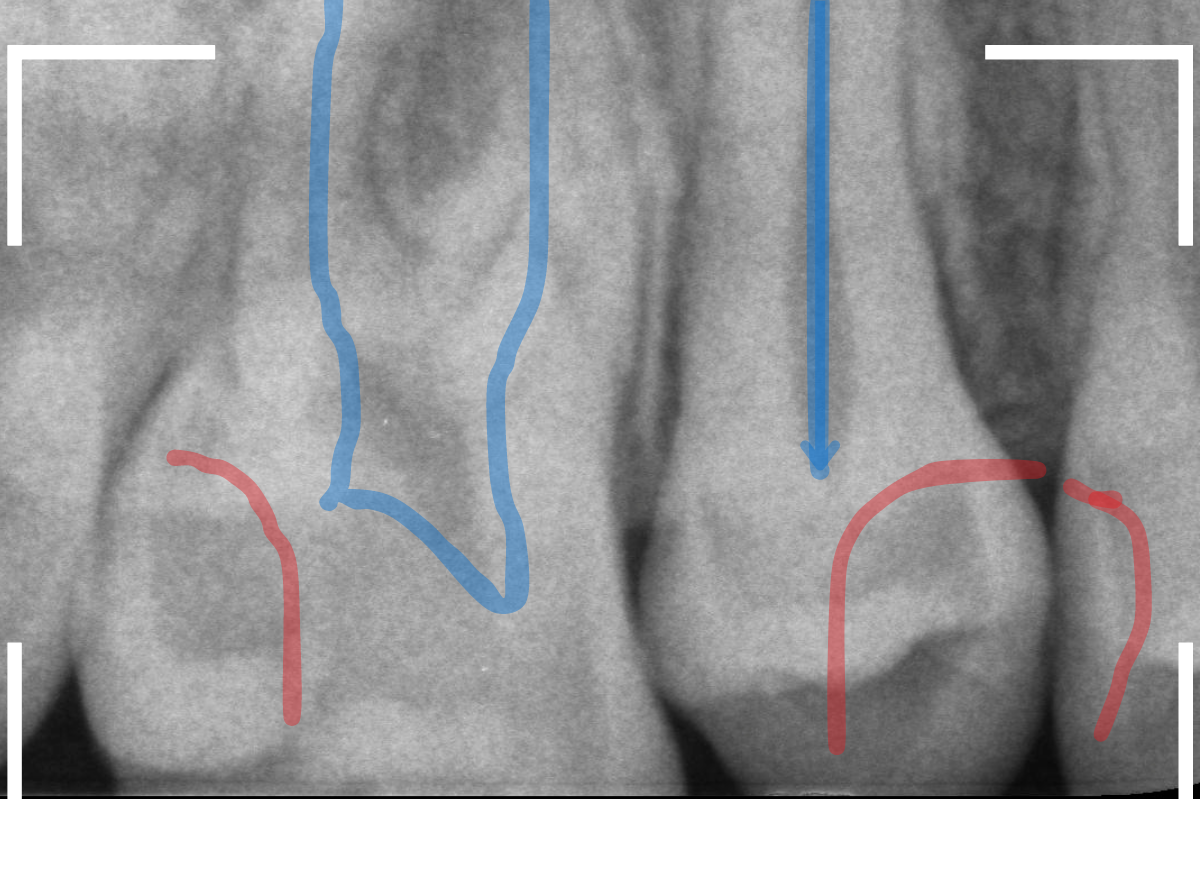

レントゲン写真で確認します。

青い線が神経、赤い線が虫歯の部分です。

前後の歯とも、かなり深く広い虫歯になっているのがわかります。